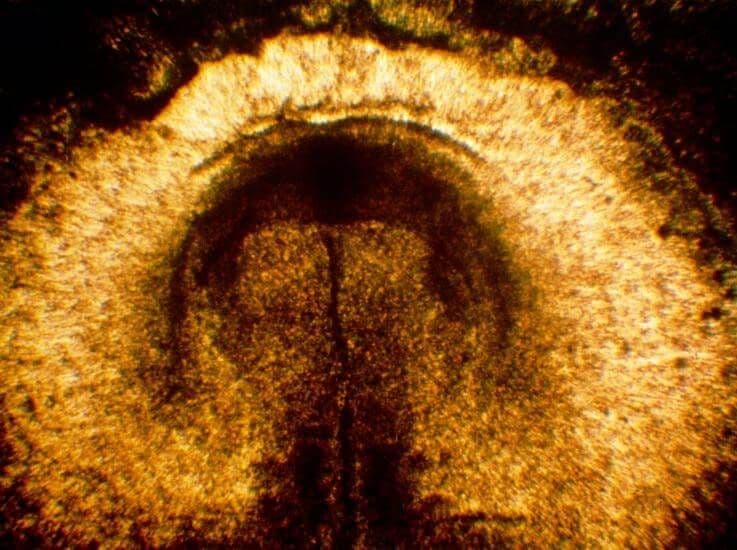

The embryo until this stage of development has consisted of two layers of cells. Now, a third layer starts to become visible as a “bulge” between the two – this bulge can be seen in the centre of this image.

Shown here is the neural tube of an embryo in the early stages of pregnancy. The brain and spinal cord will develop from the neural tube. If the tube does not fully close, it can lead to birth defects, most commonly spina bifida.

While you’re busy coming to terms with being pregnant, there are incredible changes taking place inside you. The group of cells that will become your baby is currently shaped as a flat disc and undergoing significant development. A narrow groove begins to form down the middle of the cells. The leading edge of the groove is slightly wider, forming a circular “node”. The outer edges of the node and groove are slightly raised. The cells move from the rolled edges of these structures downwards into the groove to lie between the original two layers of cells. This creates three layers of cells, those on each outer disc surface and those sandwiched between them. The node and groove do not extend along the entire length of the disc.

At the head end, a separate groove forms. Called the neural groove, this ultimately forms the brain and spinal cord (the central nervous system). In four days’ time, the disc will lengthen and widen at the end that will form your baby’s head. In six days’ time, the neural groove has folds on either side that will later meet to form the neural tube.